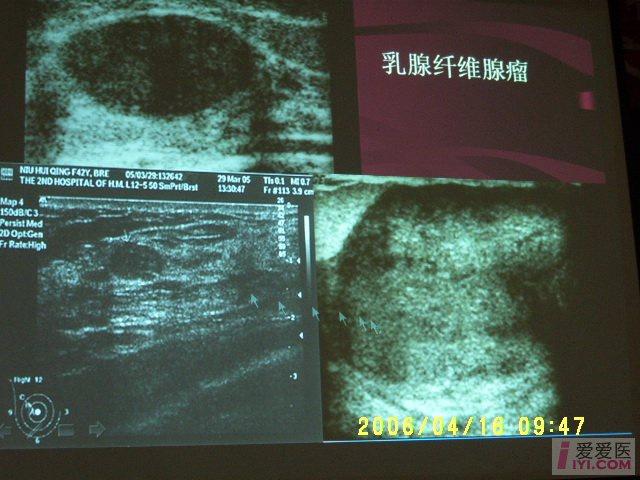

可能你见过一些乳腺管状腺瘤的超声表现但这些病例真的不一样

图片尺寸779x606